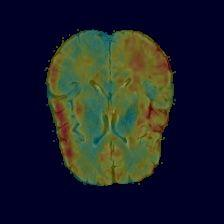

Current unsupervised anomaly localization approaches rely on generative models to learn the distribution of normal images, which is later used to identify potential anomalous regions derived from errors on the reconstructed images. However, a main limitation of nearly all prior literature is the need of employing anomalous images to set a class-specific threshold to locate the anomalies. This limits their usability in realistic scenarios, where only normal data is typically accessible. Despite this major drawback, only a handful of works have addressed this limitation, by integrating supervision on attention maps during training. In this work, we propose a novel formulation that does not require accessing images with abnormalities to define the threshold. Furthermore, and in contrast to very recent work, the proposed constraint is formulated in a more principled manner, leveraging well-known knowledge in constrained optimization. In particular, the equality constraint on the attention maps in prior work is replaced by an inequality constraint, which allows more flexibility. In addition, to address the limitations of penalty-based functions we employ an extension of the popular log-barrier methods to handle the constraint. Comprehensive experiments on the popular BRATS'19 dataset demonstrate that the proposed approach substantially outperforms relevant literature, establishing new state-of-the-art results for unsupervised lesion segmentation.